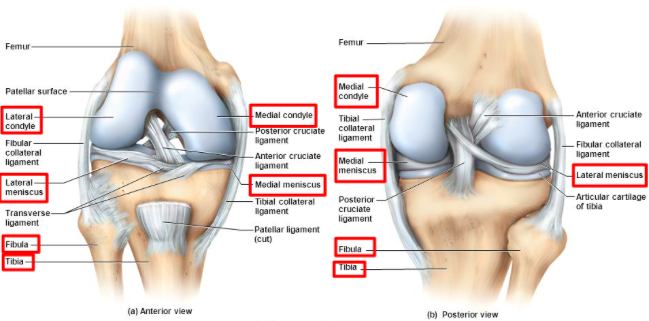

Identify the structures visible on the anterior surface of the distal femur

Identify the structures visible on the posterior surface of the distal femur

Describe the articulations of the medial and lateral condyles of the distal femur

Describe the structure and function of the intercondylar fossa in the distal femur

Where do the posterior and anterior cruciate ligaments of the knee attach to on the distal femur?

- Facet for attachment of anterior cruciate ligament – found on the lateral wall of the intercondylar fossa (smaller)